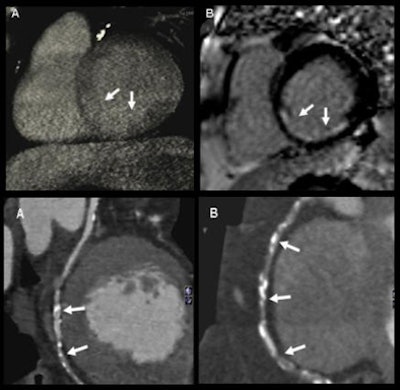

| Qualitative analysis: CT perfusion correctly classified 54 perfusion defects. Values for detecting myocardial perfusion defects at CT (versus SPECT) compared to MRI were as follows: 86% (84%) sensitivity, 98% (92%) specificity, 93% (88%) positive predictive value, and 94% (92%) negative predictive value. |

| Semiquantitative analysis: There were significant differences in upslope of signal intensity over time curve between normal and ischemic myocardium both with CT (above) and MRI (below). |

| Absolute quantification: Quantitative analysis showed significant differences in myocardial blood flow between normal and hypoperfused myocardium (p < 0.001); moderate correlation between absolute myocardial blood-flow quantification and upslope of signal intensity over time curves (r = 0.47, p < 0.01); and moderate correlation between myocardial blood flow and semiquantitative upslope for hypoperfused and normal myocardium (r = 0.41, p < 0.01 versus r = 0.43, p < 0.01). |

In the quantitative analysis, CT perfusion correctly classified 54 perfusion defects of the 60 identified by MRI, yielding 86% sensitivity and 98% specificity. At the semiquantitative analysis, the group found significant differences in the upslopes of the signal intensity of the time curve between normal and ischemic myocardium of both CT and MRI, Weininger said. In the absolute quantification of myocardial blood flow, CT was again able to differentiate between normal and ischemic myocardium, he said.

"Adenosine stress dynamic myocardial CT perfusion is, first of all, technically feasible; it can differentiate between healthy and diseased myocardium, it allows evaluation of semiquantitative and quantitative data similarly to MRI, and it seems to be particularly promising for absolute quantification of myocardial blood flow," Weininger said.